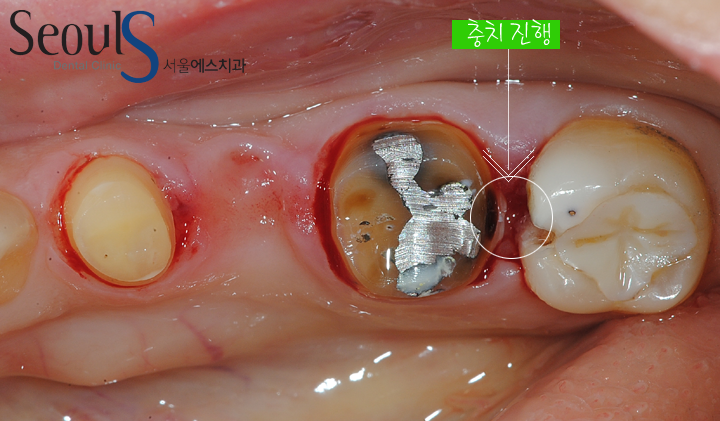

타 치과에서 브릿지 치료를 받았는데

브릿지 속으로 충치가 진행되었습니다

타 치과에서 브릿지 치료를 받았던 모습입니다

타 치과에서 브릿지 치료를 받았던 모습입니다

브릿지 가운데 보철물 형태가 어색하고

원으로 표시한 부분에 통증이 있었습니다

내원하신 이유는 통증입니다

맨 끝 어금니와 그 옆 어금니에 충치가 진행되고 있습니다

치료를 위해서 브릿지를 제거했습니다